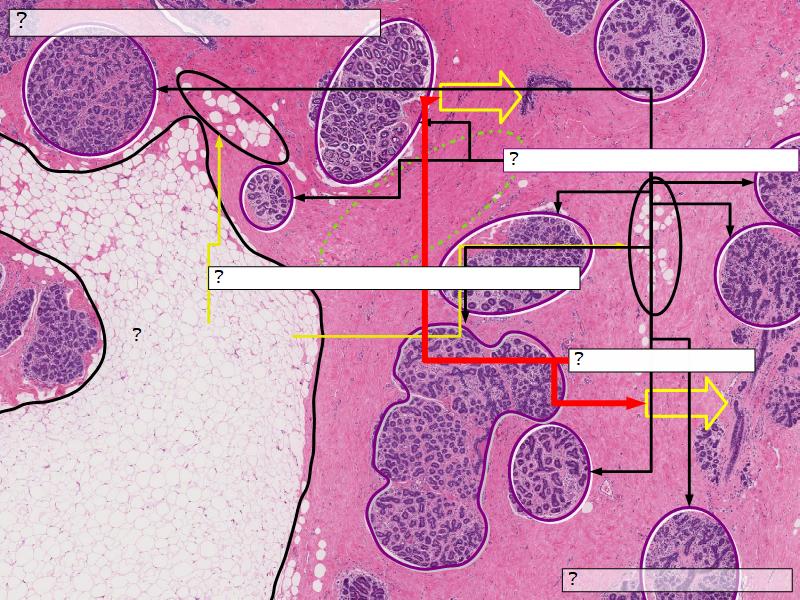

Structures

List the structures and cells found in the mammary gland.

Structures

- Lactiferous sinuses

- Stratified squamous near opening on skin

- Stratified cuboidal other parts

- Lactiferous ducts

- Stratified cuboidal

- Myoepithelial cells

- Underlie lactiferous ducts in most areas

- Basal lamina

- Separate epithelial components from stroma

Active gland

- Much larger than resting phase

- Terminal ducts proliferate to form alveoli

- Alveoli

- Surrounded by incomplete myoepithelial cells

Alveolar cells

- Apocrine secretion

- Active state

- Resting state